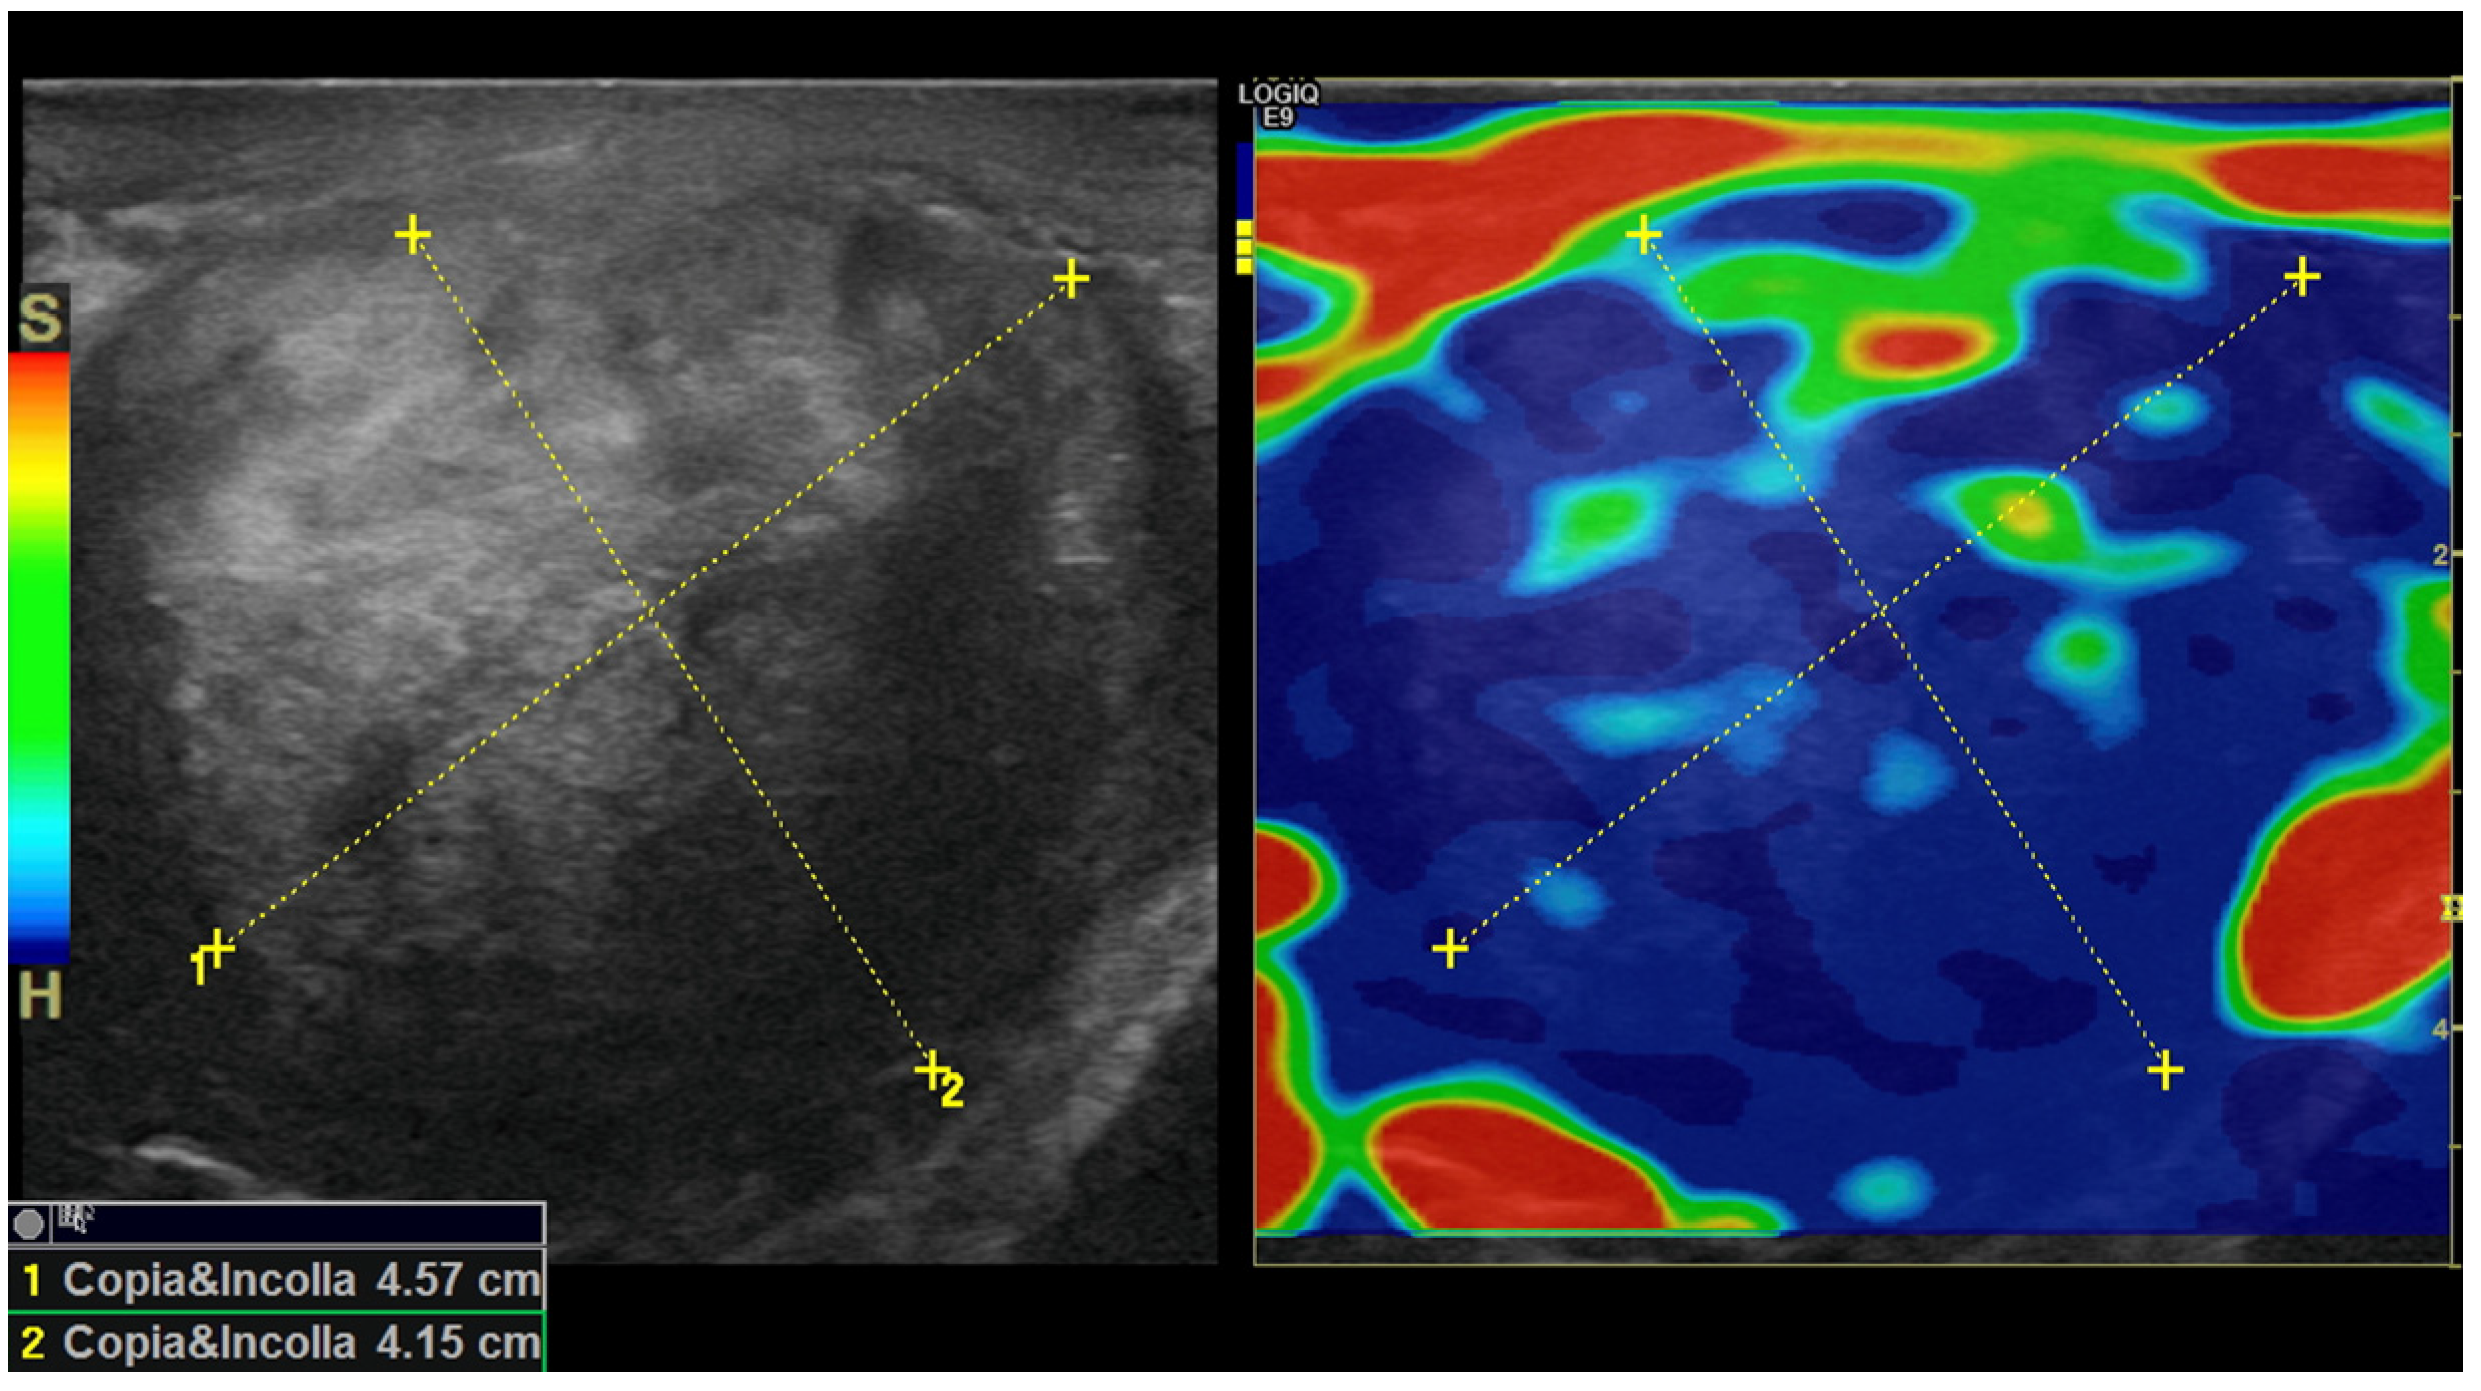

In addition, real-time strain elastography (SE) was carried out as an additional diagnostic tool for evaluating tissue elasticities when conducting US. Specifically, SE was performed by employing repeated compressions and decompressions with the transducer using a freehand technique. The pressure applied was adjusted according to the visual indicator for compression presented on a video screen. Tissue elasticity was calculated in real-time, and stiffness of tissues was displayed as a color-coded overlay on the B-mode image. During SE imaging, it was observed that the lesion was stiffer than the surrounding tissue (constituting a hard pattern) and was larger in size on the elastogram than on the B-mode US image, showing an E/B ratio > 1. Then, SE images of the lesions were assigned an elastographic five-point color score according to the distribution and degree of strain suggested by Itoh et al. for breast disease [7,8,9]. As there was no strain in the entire solid lesion and in the surrounding area, it was scored 5 and considered malignant (Figure 5).

Figure 5. Strain elastogram obtained using a 15 MHz high-frequency transducer. The image on the left of the dual display is a conventional B-mode image. The image on the right is an elastogram. A color scale was applied, for which blue corresponds to the stiffest tissue (hard). A copy or shadow function (“copia e incolla” in Italian language) was used to “duplicate” the measurements from the B-mode image and map them to the same location on the elastogram. This function helps to confirm the location of a lesion in an elastogram or vice versa. The E/B ratio was determined as 10.2 mm on the B-mode image and 14.3 mm on the elastogram, resulting in an E/B ratio of 1.4, which is suggestive of a malignancy.